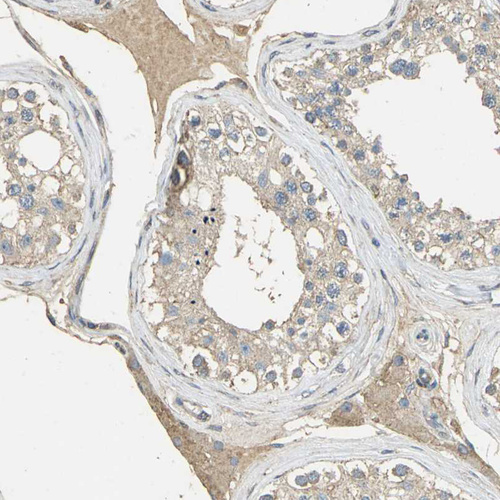

Immunohistochemical staining of human cerebral cortex shows moderate granular cytoplasmic positivity in neurons.